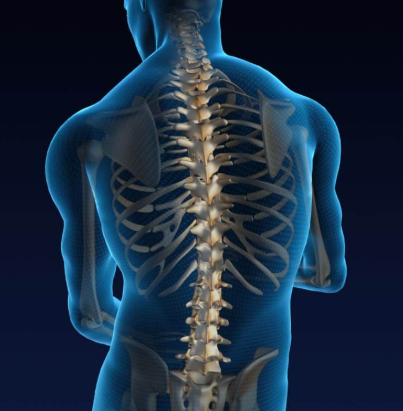

1. 척추의 정렬과 균형

건강한 척추는 옆에서 보면 S자 형태를 유지합니다. 하지만 전방전위증이 생기면 하부 요추가 앞으로 밀리며 이 곡선이 깨지고, 허리 뒤쪽 근육이 과도하게 긴장해 통증이 발생합니다.